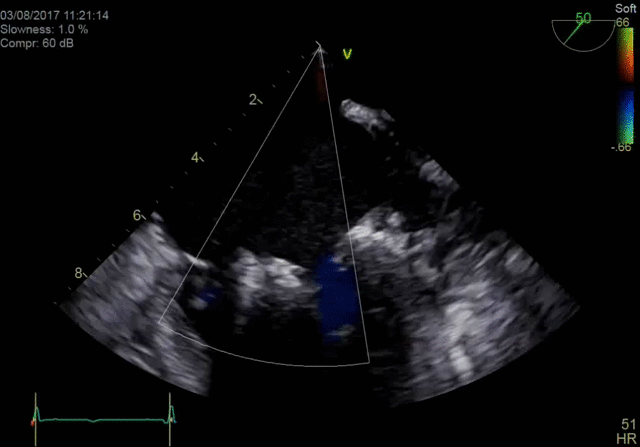

4D color imaging with the 4Vc-D probe